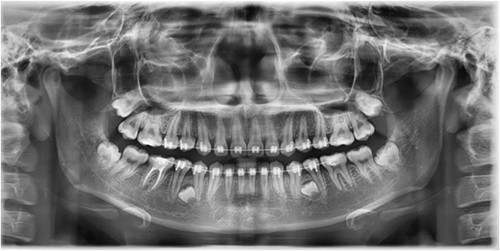

A 21-year-old patient with a non-contributory history reported to the clinic with a complaint of spacing in the anterior teeth. On radiographic examination, eumorphic supernumerary premolar crowns were found located between the roots of the mandibular first and second premolars (Fig. 1). The patient was completely asymptomatic and had no knowledge regarding the presence of these accessory teeth.

Image depicting the supernumerary premolar buds located between the first and second mandibular premolars.